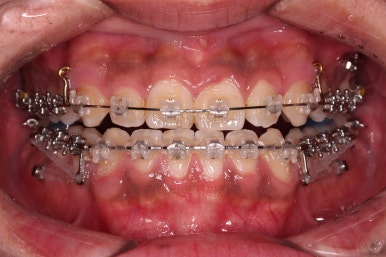

부산교정 장치를 부착했습니다.

이번에 선택하신 장치는 자가결찰 세라믹 장치에요. 스스로 철사를 묶는(결찰) 뚜껑이 달린(자가) 세라믹 성분의 장치인데요.

기능적으로도 우수하고, 세라믹이다 보니 미적으로도 장점이 있습니다.

이번 환자분은 엠파워 클리어라고 하는 장치를 사용했으며 흔히 아신느 클리피씨와 동일한 계열의 장치입니다.

장치 부착 직후의 느낌 참고해 주시고요.